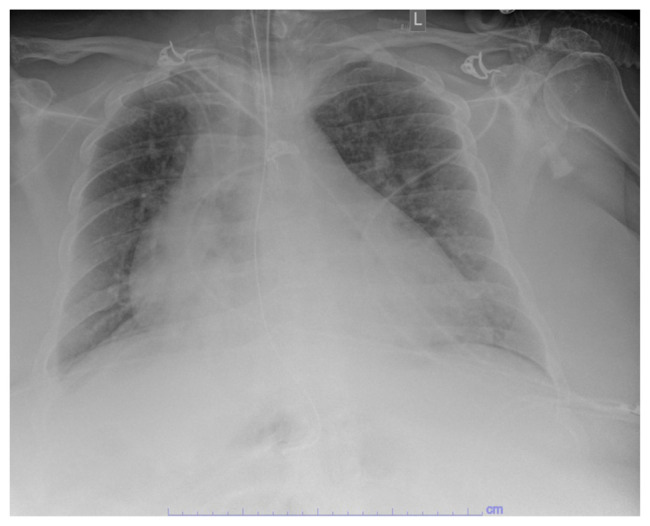

Abstract Image